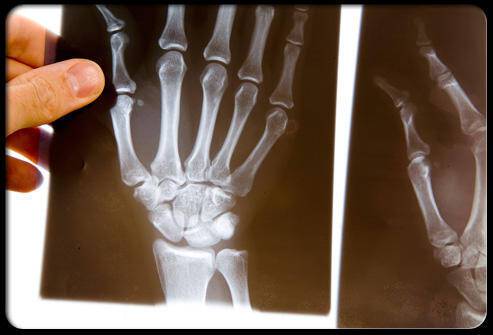

Jednou z nejznámějších příčin necitlivosti prstů je syndrom karpálního tunelu. V oblasti zápěstí se nachází úzký prostor, tzv. karpální tunel, tvořený zápěstními kostmi a pevným vazivovým pruhem. Právě tudy prochází středový nerv, který zajišťuje citlivost části ruky a prstů.

Jakmile v tomto prostoru dojde k otokům či zúžení – typicky v důsledku přetěžování ruky, opakovaných pohybů, ale i hormonálních změn – nerv se začne dráždit. To se projevuje nejprve brněním a necitlivostí prstů, zejména v noci nebo při práci, později může dojít i k oslabení úchopu a vypadávání předmětů z ruky. Neléčený syndrom karpálního tunelu může vést k trvalému poškození nervu.

Necitlivost prstů může vzniknout i tehdy, když je periferní nerv vystaven nadměrnému tlaku. Tento stav se často pojí s chronickou bolestí zad, tzv. lumbagem, nebo s potížemi v oblasti krční páteře (cervikální syndrom). Vyhřezlá ploténka, svalový spasmus či změny na obratlích mohou nerv utlačovat a narušit jeho funkci.

Výsledkem jsou pak různé neurologické projevy – od bolesti vystřelující do končetin až po brnění a ztrátu citu v prstech. Včasná diagnostika (například pomocí zobrazovacích metod) je zásadní, protože dlouhodobý tlak může nerv trvale poškodit a obtíže pak nemusí být plně vratné.